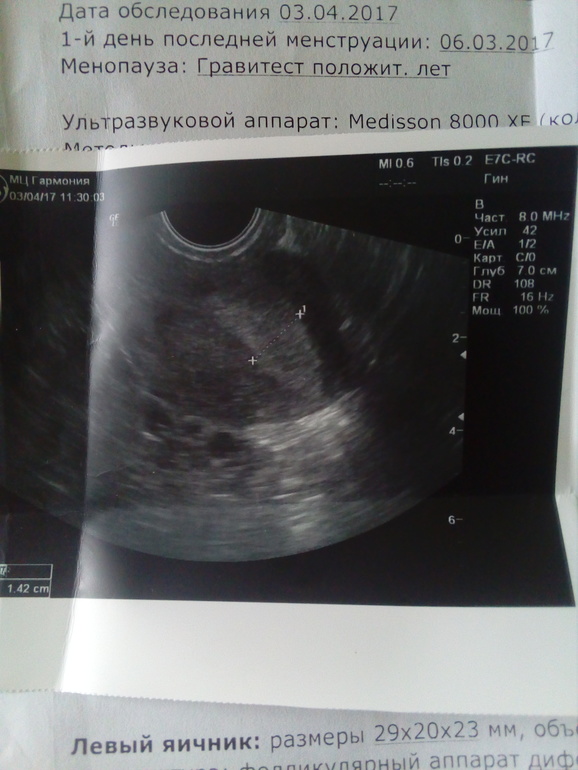

Привет, девочки...помогите разобраться с УЗИ. Сегодня ходила...10 дц. К врачу только 6 февраля(((